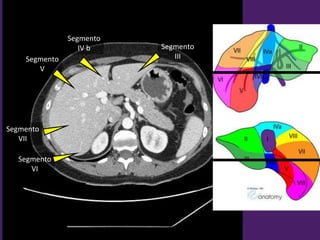

Bonus track:

Segmentación

del hígado

Vista Anterior. Vista Posterior.

Segmentación hepática

Vista superior Vista inferior

Segmento

II

III

IV a

VIII

VII

IV

I

Receso de

Rex

IV b

V

VI

L1-L2

L2